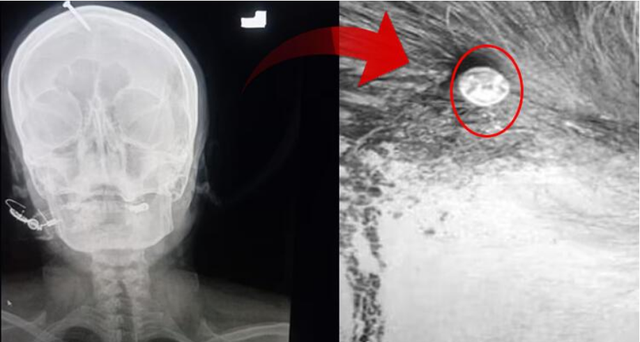

Një grua shtatzënë në Pakistan përdori një metodë të pabesueshme dhe çnjerëzore për të lindur djalin e saj të katërt pas tre vajzave. Ajo u shtrua në Spitalin Lady Reading në qytetin Peshawar me një gozhdë 5 cm në kokë.

Gruaja, identiteti i së cilës nuk bëhet i ditur, e gjeti veten pranë një “sheruesi” pas kërcënimeve të të shoqit. I ashtuquajturi shërues i tha gruas se për të pasur një djalë, ajo duhej të ngulte një gozhdë në kokën e saj. Gozhda iu ngul me çekan në kokë.

Mjeku Haider Khan shpjegoi se gruaja shtatzënë u përpoq të hiqte gozhdën nga koka me pincë, por dështoi dhe shkoi në spital. “Ajo ishte plotësisht e vetëdijshne kur arriti këtu, por kishte shumë dhimbje. Për fat të mirë nuk i ka prekur trurin”, tha mjeku.